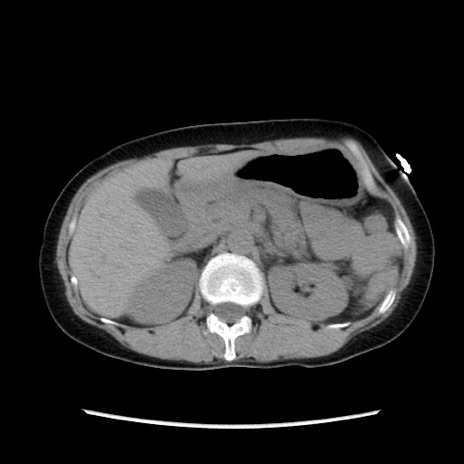

症例32(横断像)

【症例】40歳代 女性

【主訴】上腹部痛、嘔気・嘔吐

【現病歴】約9時間前頃から急に上腹部痛、嘔気、嘔吐が出現。改善しないため救急要請。

【既往歴】子宮頚癌(広汎子宮全摘術、放射線療法)、腸閉塞

【身体所見】腹部:平坦、軟、腸雑音亢進、上腹部を中心に腹部全体に圧痛あり。

【データ】WBC 8400、CRP 0.03